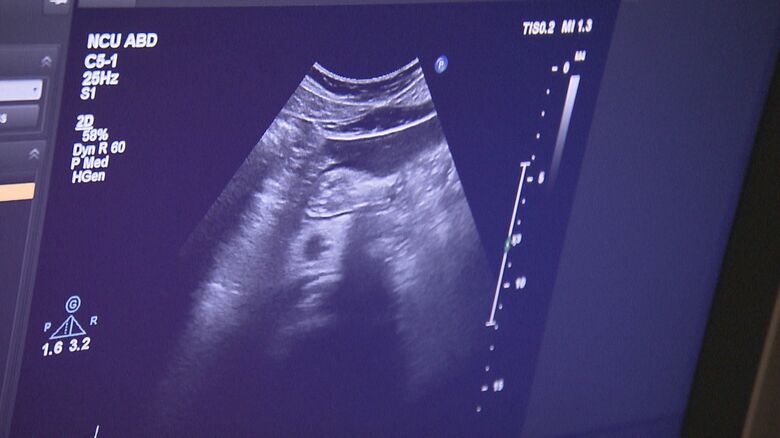

生活習慣改善のきっかけに…名古屋市がワンコイン検診に“腹部… ギャラリー 1/12 記事に戻る 2/12 記事に戻る 3/12 記事に戻る 4/12 記事に戻る 5/12 記事に戻る 6/12 記事に戻る 7/12 記事に戻る 8/12 記事に戻る 9/12 記事に戻る 10/12 記事に戻る 11枚目以降の画像を見る 1 2